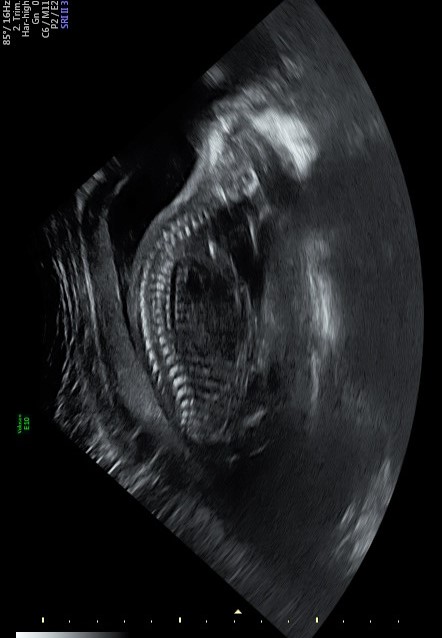

I'm leaning toward girl on this one. The potty shot shows 3 lines, although potty shots are not as accurate at this gestation.

I too am leaning more girl than boy but am no expert 😆